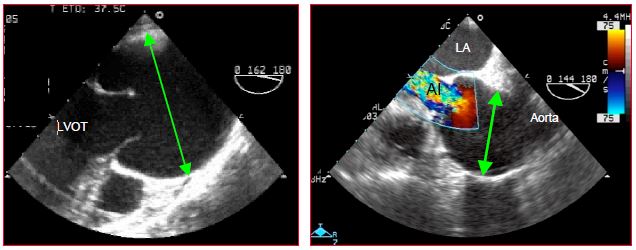

For further information, reference may be made to Chapter 14 (Paediatric cardiac surgery). Illustrations are taken from transesophageal echocardiography (TEE), which anaesthetists may perform in the operating theatre.